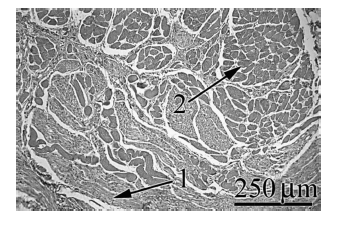

Com base no corte histológico mostrado na figura acima, julgue os itens que se seguem.

Todas as células desse tecido apresentam interações com glândulas, apesar de tais estruturas não serem exibidas na figura.